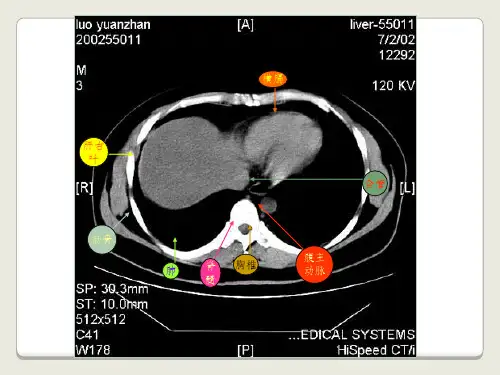

医学影像学上腹部CT概述上腹部CT扫描是一种用于诊断上腹部疾病的医学影像技术。

上腹部包括肝脏、胆囊、胰腺、脾脏、肾脏等重要器官,因此上腹部CT扫描对于这些器官的疾病诊断具有重要意义。

技术上腹部CT扫描使用X射线和计算机技术,对腹部进行断层扫描。

扫描时,X射线会穿过患者的身体,并在计算机中形成图像。

通过断层扫描,可以获得患者腹部各个器官的清晰图像,从而帮助医生诊断疾病。